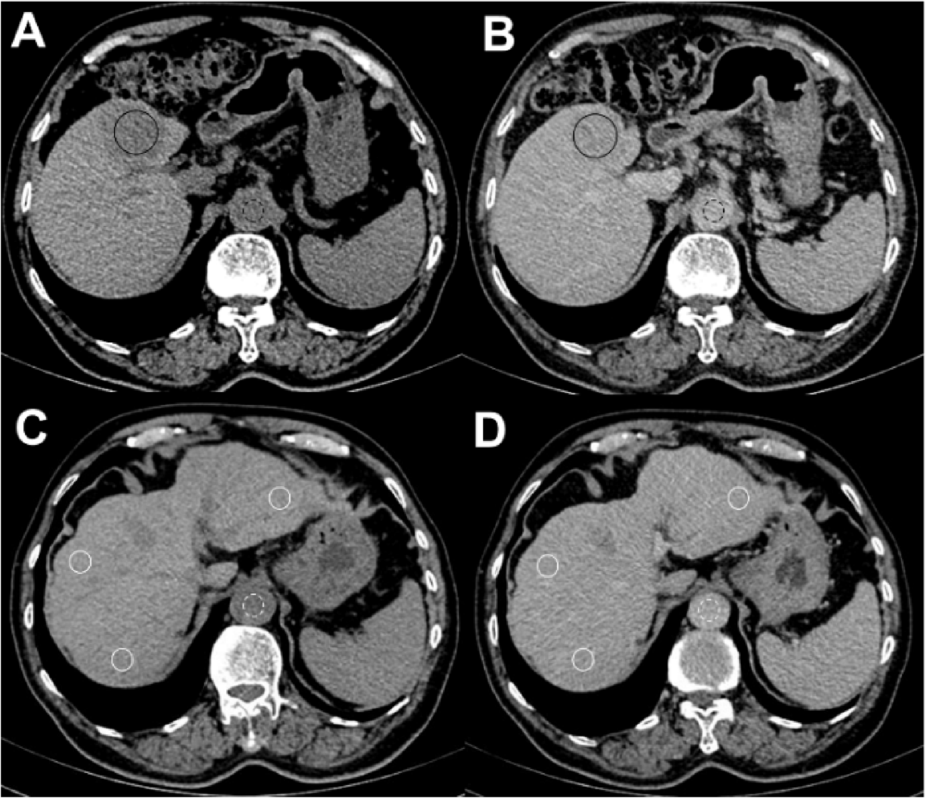

Fig. 1

ECV fraction position of a 79 years old male with hepatocellular carcinoma receiving immune checkpoint inhibitors. Axial unenhanced (A) and equilibration contrast-enhanced CT (B) show ROIs on the 4.5 centimeters tumor (black circle) and aorta (black dashed circle). Axial unenhanced (C) and equilibration contrast-enhanced CT (D) show ROIs on the anterior and posterior segments of the right lobe and lateral segment of the left lobe of the liver (white circle) and the aorta (white dashed circle). The tumor ECV fraction was 38.48%, liver ECV fraction was 28.07%.